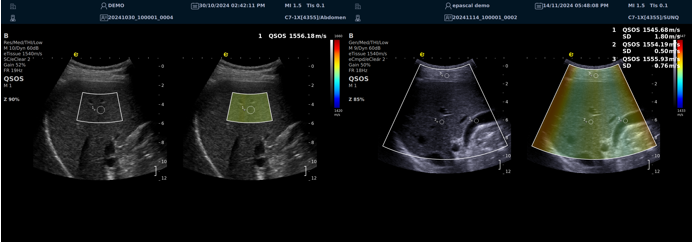

QSOS声速定量成像

测量原理

QSOS声速成像技术利用声波在组织中的传播速度差异性,计算不同位置的声速值,反映组织的物理特性。

成像过程

利用超声探头发射超声波脉冲,分析反射信号的时间延迟,确定声波传播路径和速度,构建声速分布图像。

图像显示

QSOS技术采用彩色编码显示声速图像,不同颜色代表不同声速值,便于医生识别病变部位和测量。

25fb8cb17586b86e5d915a2be3025a2.png

技术优势

?精准定量反映组织特性,成像更敏锐?彩色编码直观显示,轻松发现异常?捕捉声速差异,早期、微小病变更易察觉

肌骨22.png

肌骨领域的应用

?精准定位损伤部位?判断损伤严重程度?监测肌肉营养?评估肌少症?骨质疏松评估

08bce87534cf2cf9f10c1dfc5b314dd.png